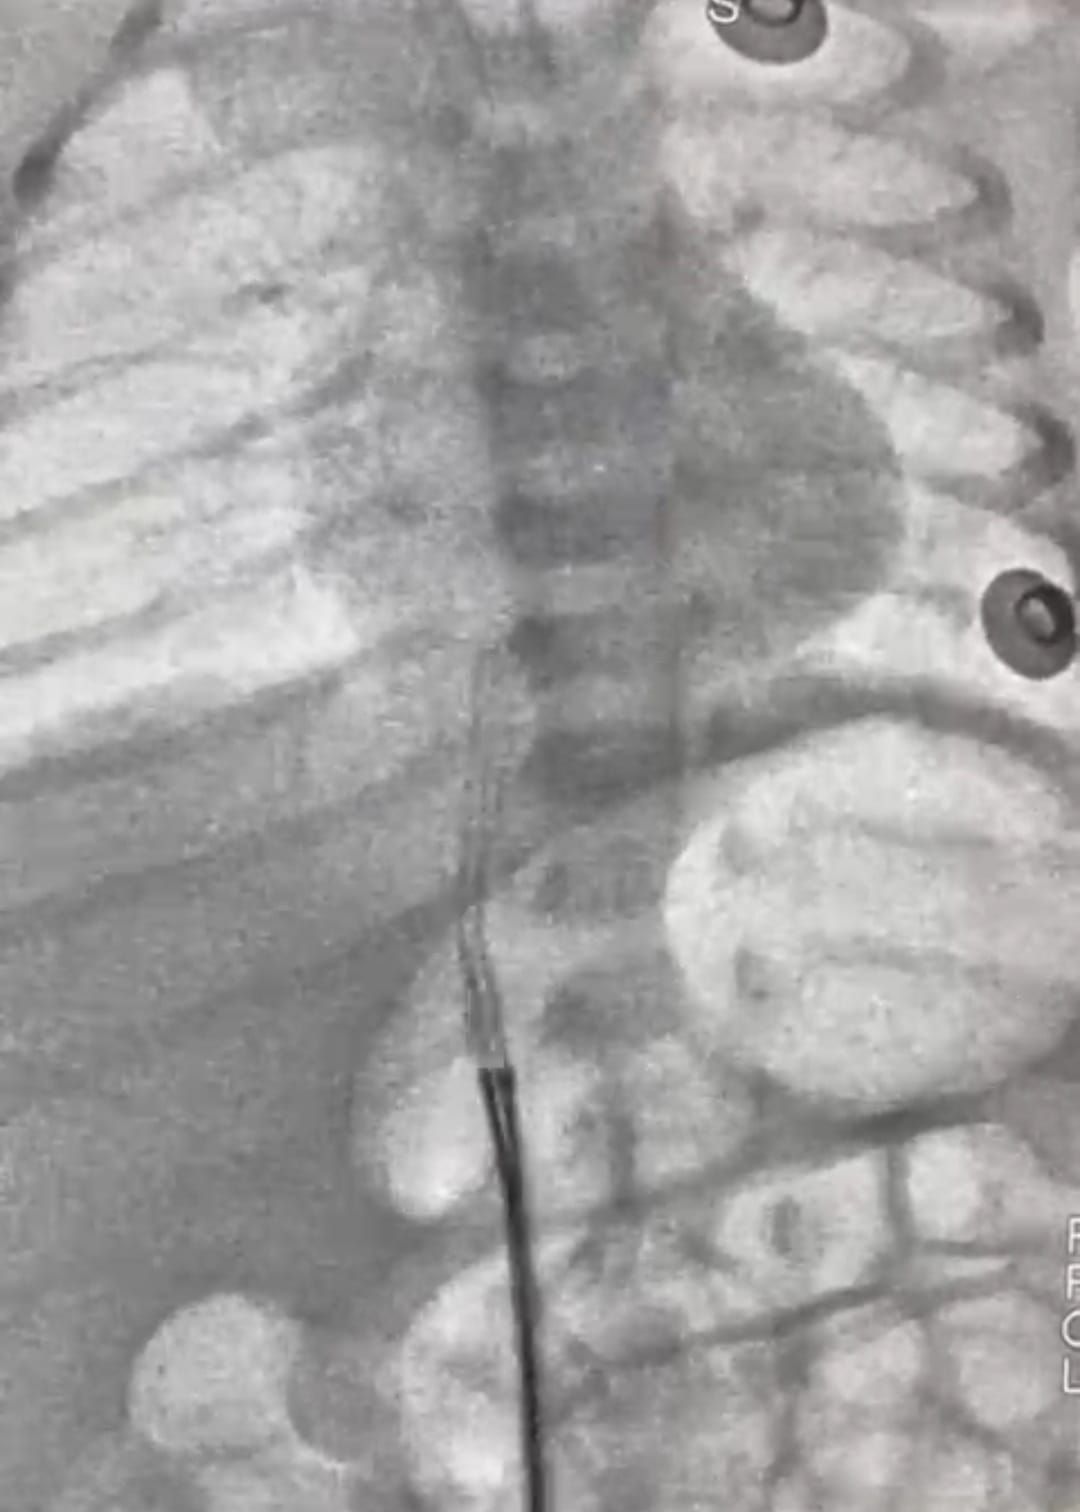

وأفاد الدكتور محمد عبد الهادى عميد معهد القلب القومى بأن طفل حديث الولادة، يبلغ من العمر 5 أيام فقط، قد وصل إلى المعهد في حالة حرجة، بعد أن تحرك جزء من قسطرة السرة من مكانه واستقر في قلب الطفل، وهذه القسطرة تستخدم أحياناً لإدخال السوائل والأدوية، وقد استدعت هذه الحالة تدخلاً سريعًا ودقيقًا، وعلى الفور قام فريق عمل الحضانة،، فى التنسيق لدخول الحالة أول أيام العيد وتجهيزها للتدخل الجراحى، وقام فريق طبي متميز بإجراء القسطرة العاجلة للرضيع. وبفضل الله ومهارة الفريق الطبي، تم استخراج قسطرة السرة بنجاح ودون مضاعفات، والرضيع الآن في حالة مستقرة، وقد غادر الحضانة إلى منزله في حالة جيدة وبدون أي مضاعفات.

وأضاف عميد المعهد أنه ساهم في هذا الإنجاز الطبي فريق متكامل من الأطباء والتمريض والفنيين من أبناء المعهد تحت قيادة أ. د. أحمد معوض الإمام إستشارى القلب وقسطرة العيوب الخلقية بالمعهد، وأ. د. رشا حسني.. رئيس قسم التخدير، وأ. د. أحمد جمال ندا.. زميل التخدير، د. هبة وشاحى .. استشارى الحضانات والرعاية، ود. أحمد أبو هاشم ود. محمود صديق، ود. نعمة إبراهيم، ود. جهاد محمود.